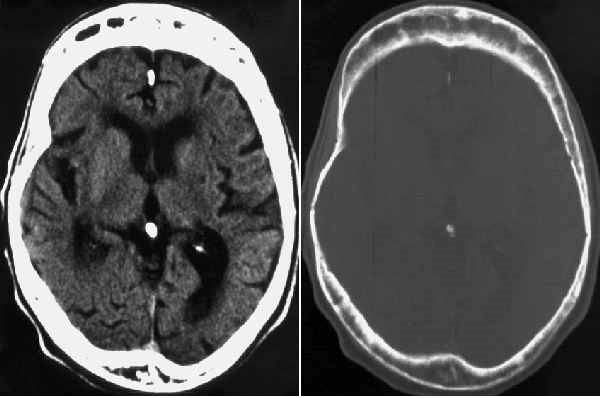

Los cambios radiográficos son patognomónicos, y suelen llevar al diagnóstico. La Fig. 80-2 muestra un húmero; la Fig. 80-3 una vértebra, la Fig. 80-4 una pelvis, y la Fig. 80-5 un cráneo afectados por la enfermedad de Paget; la Fig. 80-6 es el estudio tomográfico del mismo cráneo.

Fig. 80-6. TAC del cráneo mostrado en la Fig. 80-5.